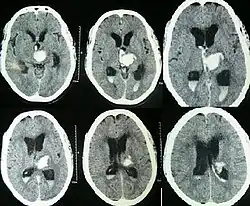

![]() Wodogłowie widoczne na obrazie TK głowy |

Wodogłowie, hydrocefalia (łac. hydrocephalus) — zwiększenie objętości płynu mózgowo-rdzeniowego w układzie komorowym mózgu, które przeważnie powoduje wzrost ciśnienia śródczaszkowego[1]. U osób starszych wodogłowie może wywoływać bóle głowy, podwójne widzenie, zaburzenia równowagi, nietrzymanie moczu, zmiany osobowości i upośledzenie umysłowe[1]. U niemowląt wodogłowie powoduje powiększanie się obwodu głowy (główka dziecka ma kształt gruszki), uwypuklenie i poszerzenie ciemiączek, poszerzenie szwów czaszkowych i opóźnienie rozwoju dziecka[1]. Inne objawy mogą obejmować wymioty, senność, napady padaczkowe oraz objaw zachodzącego słońca[1].

Wodogłowie rozpoznaje się na podstawie palpacyjnej oceny napięcia i wielkości ciemiączek, szerokości szwów czaszkowych, pomiarów obwodu główki odpowiednio do wieku na siatkach centylowych. Badaniem obrazowym, wykonywanym w pierwszej kolejności, jest ultrasonografia przezciemiączkowa, ewentualnie tomografia komputerowa lub obrazowanie metodą rezonansu magnetycznego.